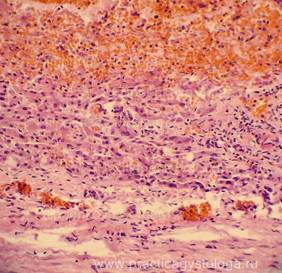

Рис. 5-8. Аденокарцинома молочной железы (различные поля зрения микроскопа с различной степенью развития соединительнотканной стромы). Труп женщины, 57 лет (тот же). Окраска: гематоксилин-эозин. Увеличение х100. Стеклопрепарат предоставлен врачом - судебно-медицинским экспертом судебно-гистологического отделения ГУЗ «Самарское ОБСМЭ» Ким С.В.